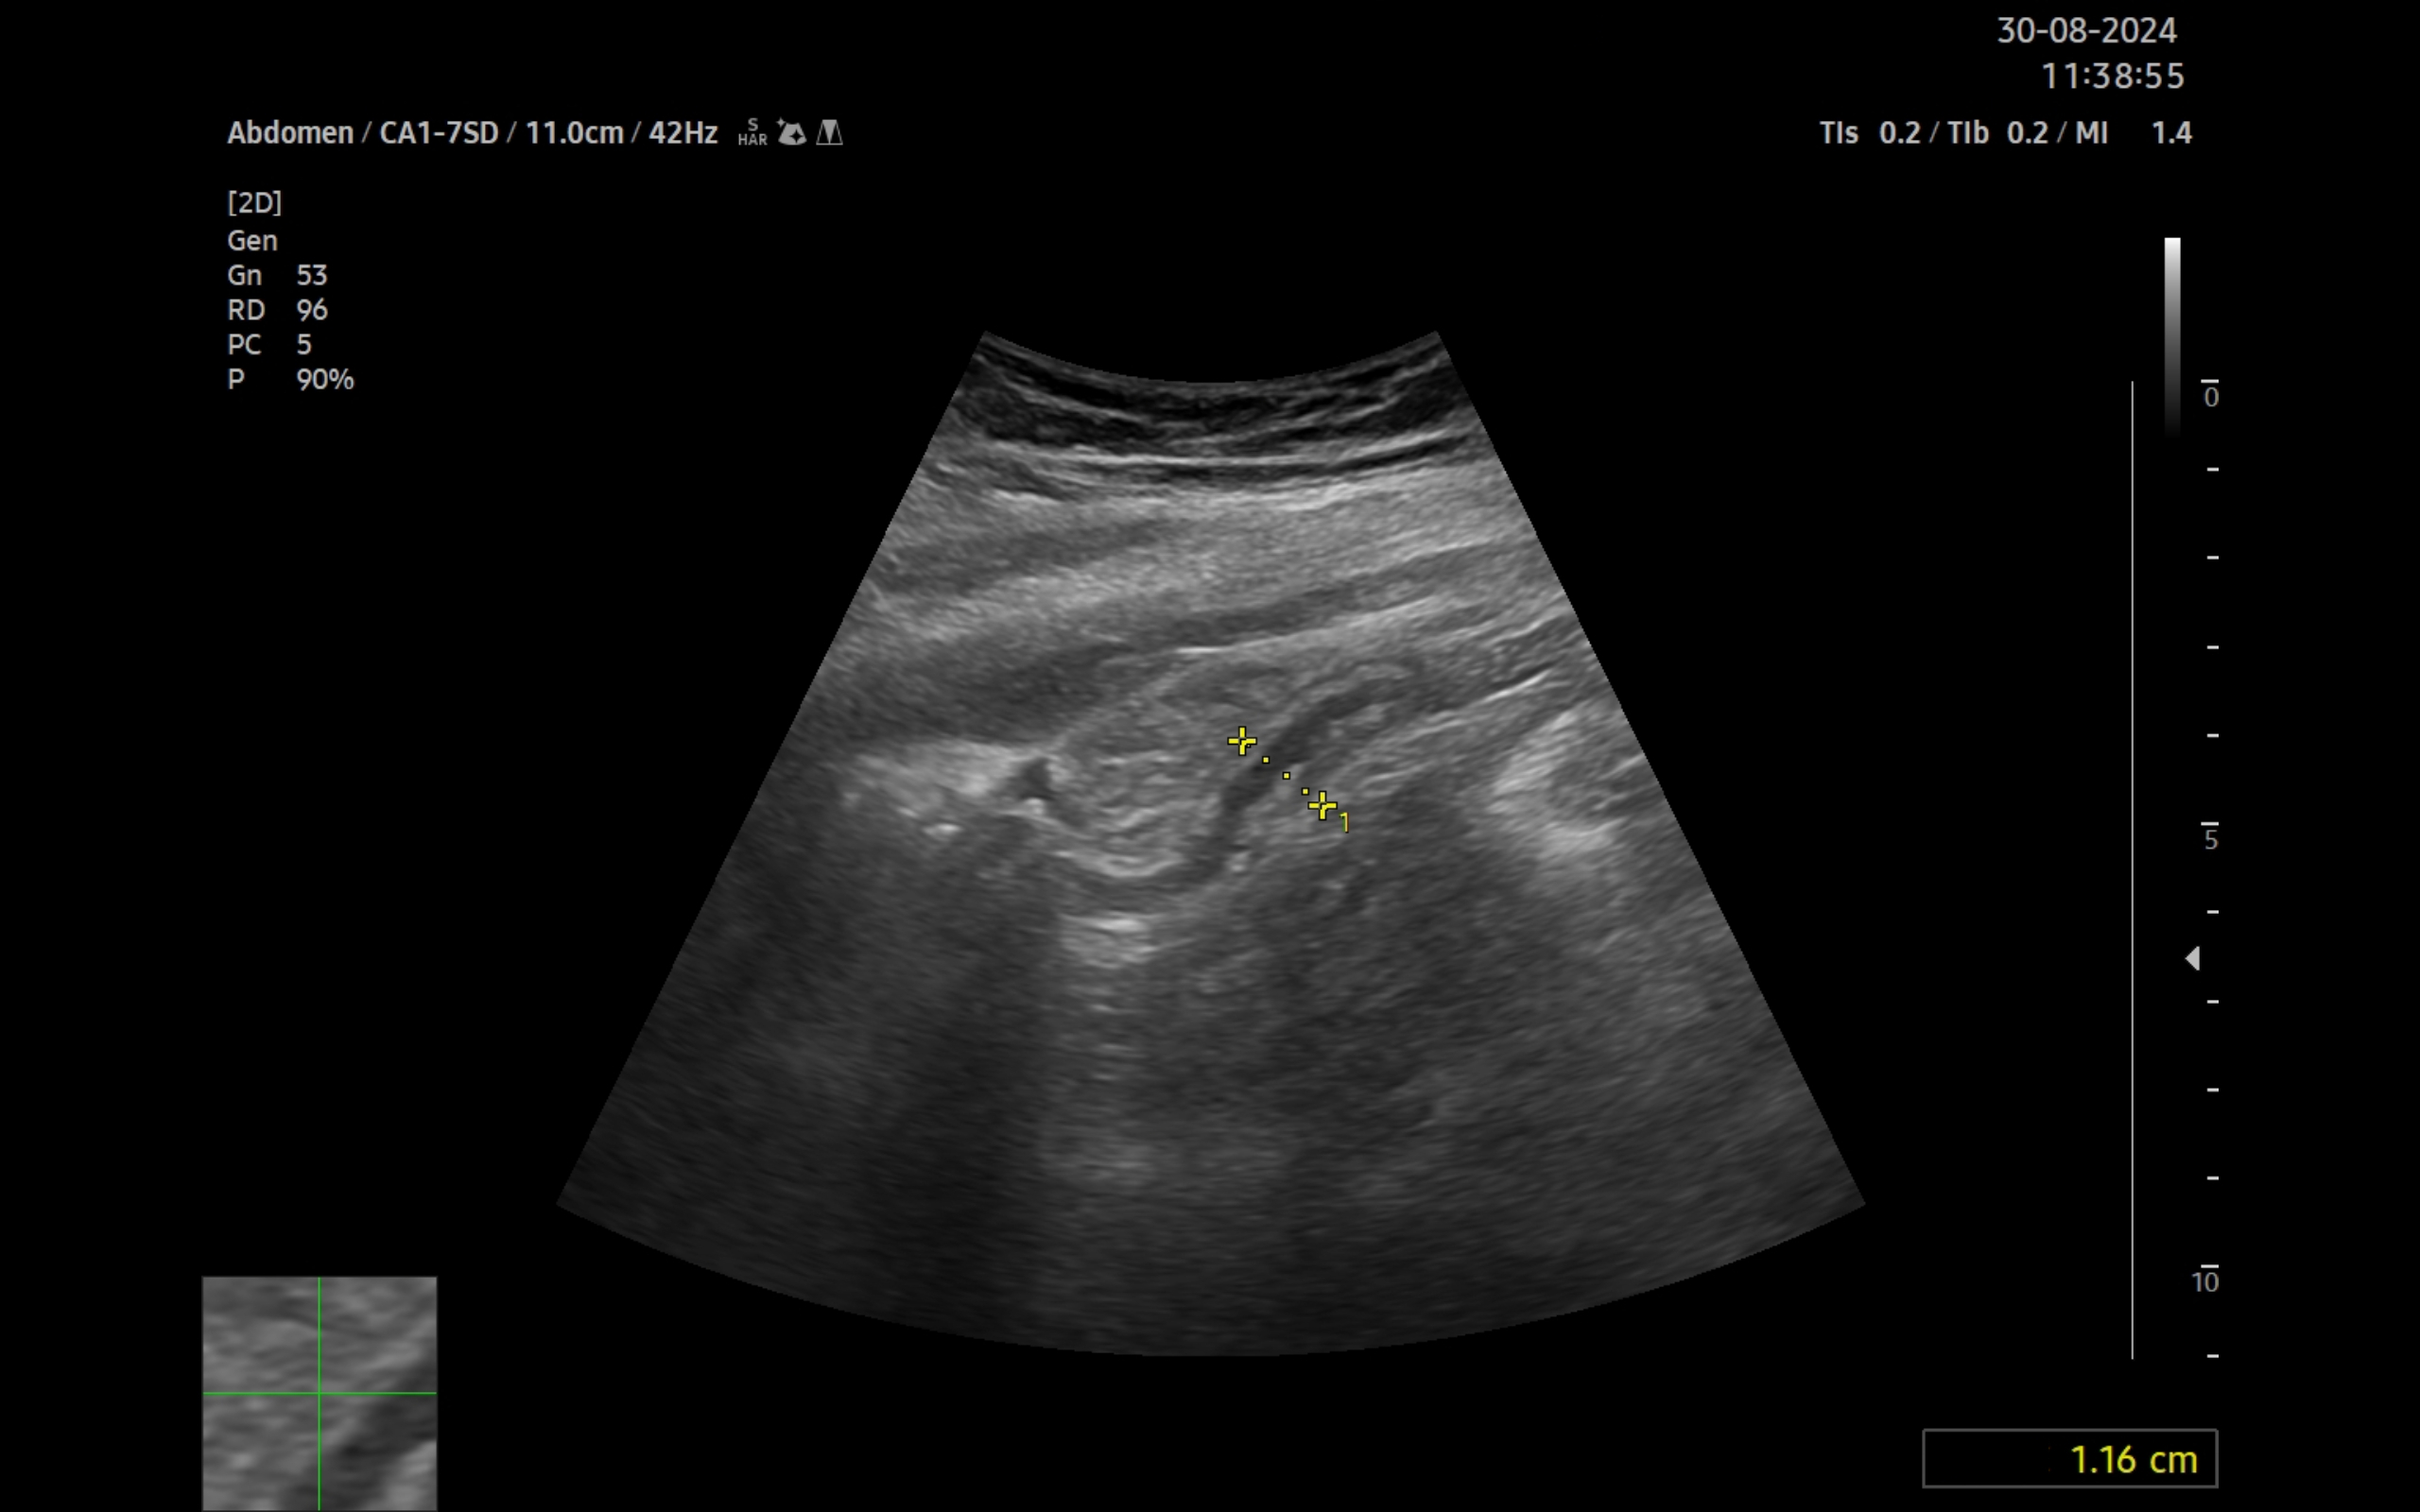

Ecografía clínica:

Imagen hiperecogénica con sombra en interior de vesícula biliar, hígado, páncreas, bazo y riñones sin alteraciones, vejiga orina poco replecionada. Llama la atención mínima imagen anecogénica en fondo de saco de Douglas. Apéndice visible en fid con diámetro 1,07 cm con captación aumentada con apendicolito con fenómeno centelleo.

La ecografía complementa la anamnesis y la exploración física. A día de hoy está disponible en la mayoría de centros de salud. En el caso concreto de la paciente, la discapacidad intelectual limitó la información obtenida de la entrevista. Ante la detección de un apéndice con diámetro mayor de 6 mm, no compresible, captación aumentada y apendicolito, se ha podido diagnosticar el proceso.